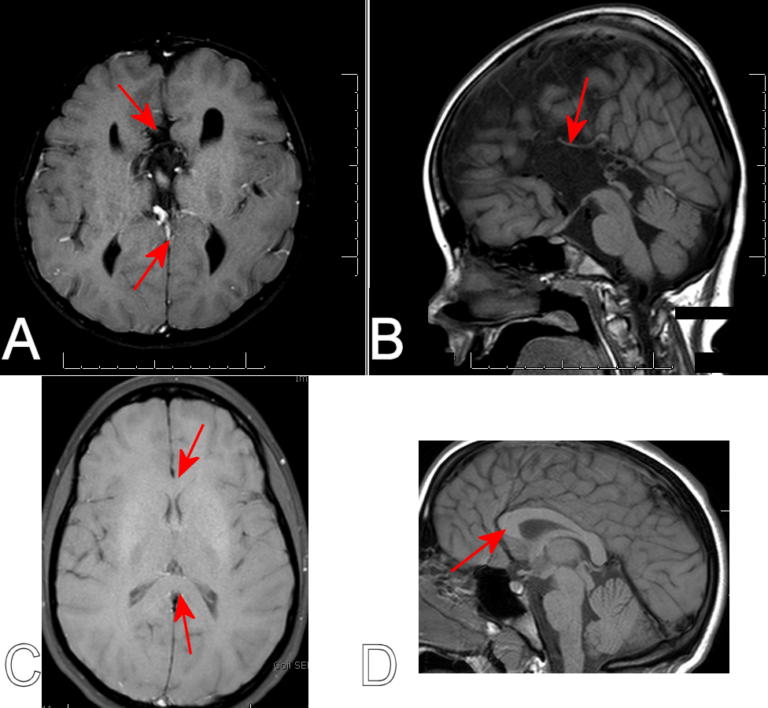

corpus callosum schizophrenia public – Neuroscience News

Primary degeneration of the corpus callosum (Marchiafava-Bignami …